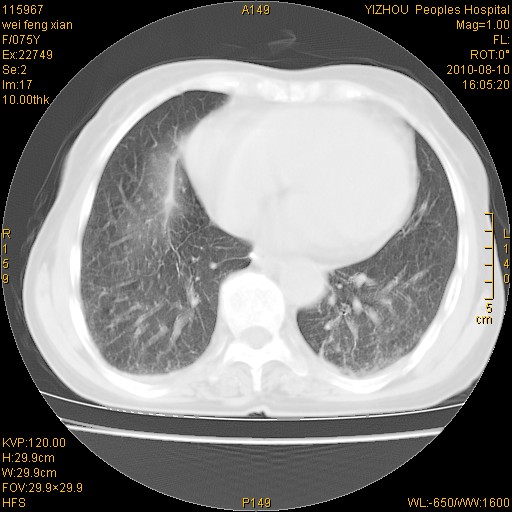

标题: CT28313:两肺弥漫性病变 [打印本页]

标题: CT28313:两肺弥漫性病变

女,75岁,患者反复头昏乏力面色苍白3年,再发10天入院。临床贫血查因。

双肺间质增生并右肺上叶炎性改变,不除外右肺上叶结核病肺内播散

考虑右肺上叶炎症合并双肺结核可能性大,建议上传纵隔窗ct图片。

双肺结核可能性大

考虑尘肺并结核;右上肺支气管扩张!

结核、尘肺、支气管肺泡癌都不能除外

右肺上叶继发性肺结核伴肺内血型播散!

考虑右肺上叶继发性肺结核伴两肺播散。